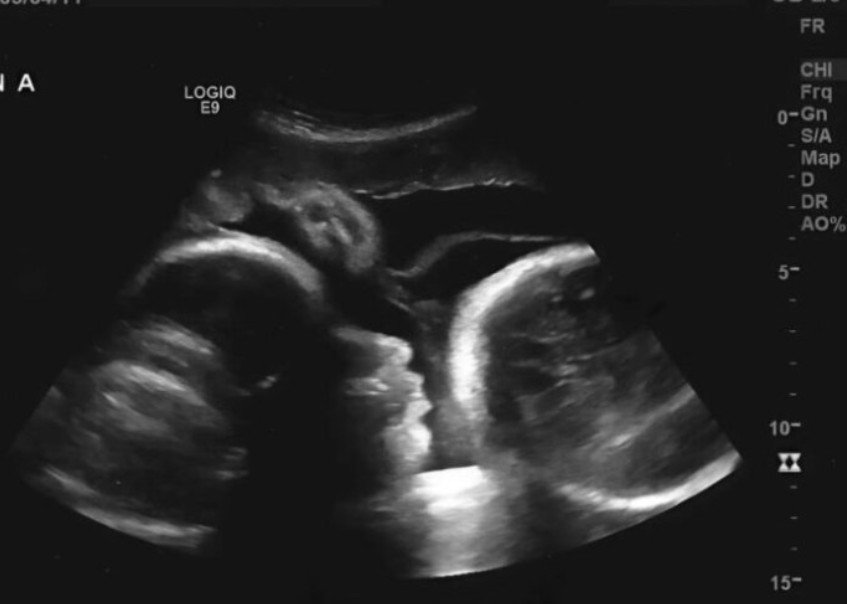

כשהביט במסך האולטרסאונד, פניו של הרופא החווירו לפתע, ובקול רועד הוא אמר את האמת הכואבת. לריסה לא הייתה בהריון; הבדיקות הראשוניות נתנו תוצאה מטעה. הנפיחות בבטנה של האישה הקשישה לא נגרמה מתינוק שגדל, אלא מגידול שחלתי מסיבי שכיסה את גופה מבפנים.

ההסבר של הרופא היה הרסני עבור לריסה. תחושת ה”תנועה” בבטנה הייתה למעשה רק הגידול שלוחץ על איבריה. יתר על כן, מכיוון שעיכבה את פנייתה לעזרה רפואית במשך זמן כה רב, תאי הסרטן התפשטו בכל גופה. הרופא הכה אותה באמת הכואבת ואמר: “אילו היית מגיעה מוקדם יותר, היינו יכולים להציל אותך, אבל עכשיו המצב קריטי.”